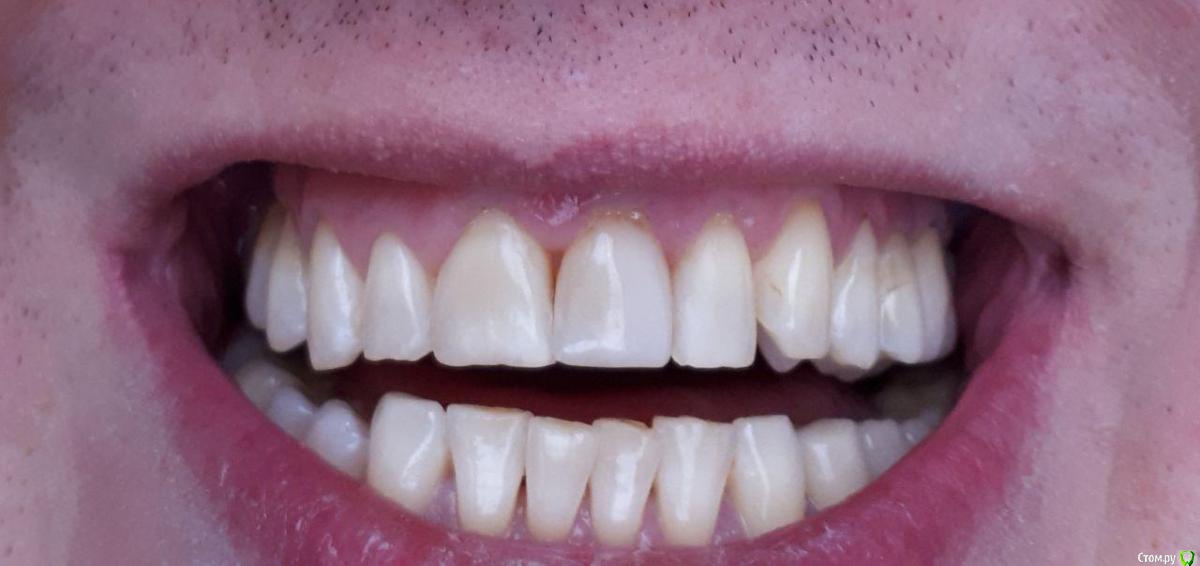

Доброго времени суток! Будьте добры, посоветуйте хорошего, опытного хирурга-пародонтолога, работающего поближе к Магнитогорску.- Челябинск, Екатеринбург, Уфа, Оренбург, Самара, который смог бы помочь мне с моей проблемой,а проблема заключается в генерализованной рецессии. Заранее Спасибо!